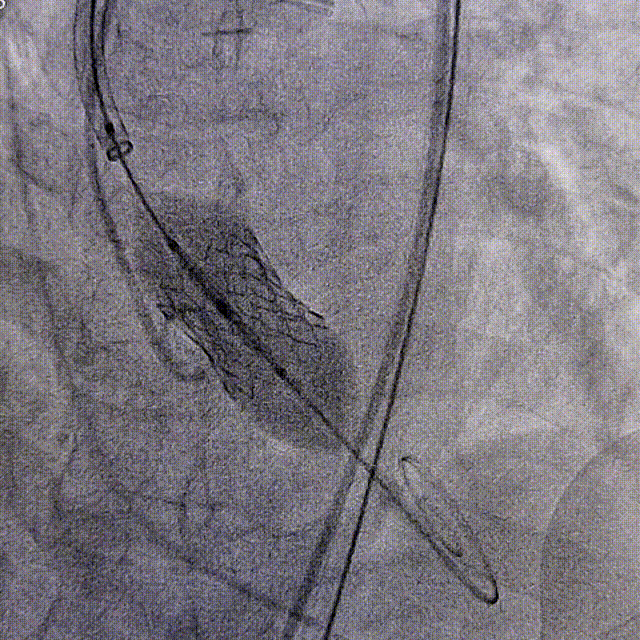

傅女士(化名),杭州人,确诊弥漫大B细胞淋巴瘤(起源于淋巴造血系统的恶性肿瘤,病情特点进展快、易转移,高危患者病情进展迅速,化疗药物常常耐药,容易复发,危及患者生命)10余年,历经多种方案治疗,疗效均不佳,期间3次复发。